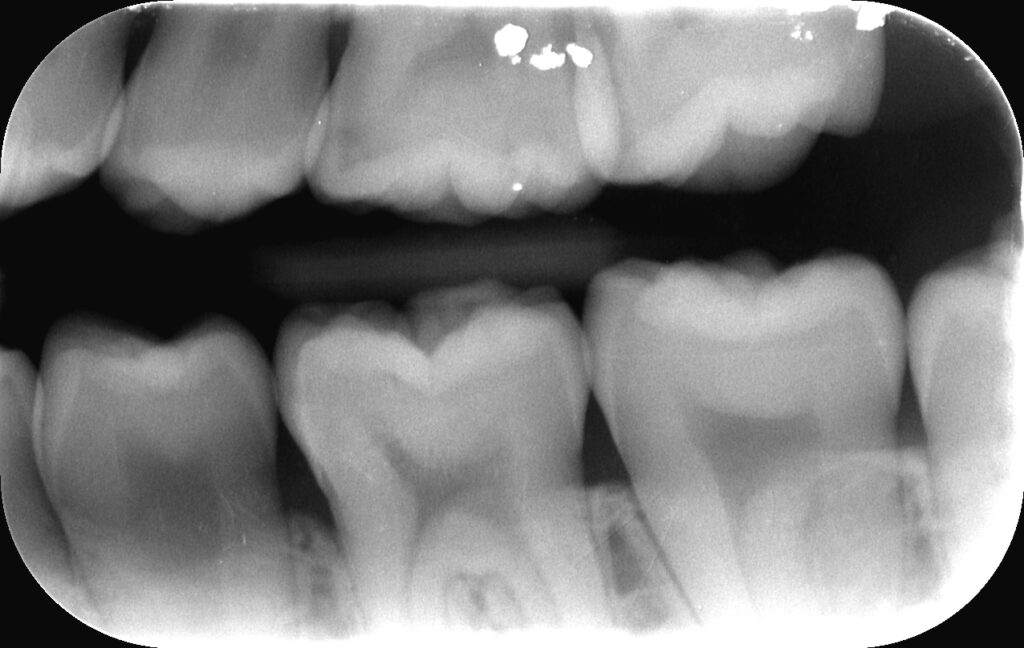

歯と歯の間のむし歯(隣接面う蝕):初期は見た目で気づきにくく、バイトウイングという撮影法が最も感度よく発見できます。

バイトウイング:上下臼歯部の隣接面むし歯や骨レベルを効率よく。むし歯の早期発見に最適。